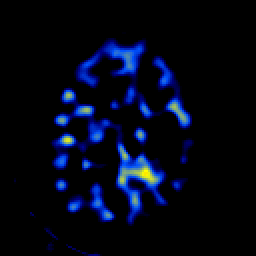

SPECT TL Study #5 -- Slice #43

[Home][Help][Clinical][Tour 1][Tour 2][Tour 3] Slice 43